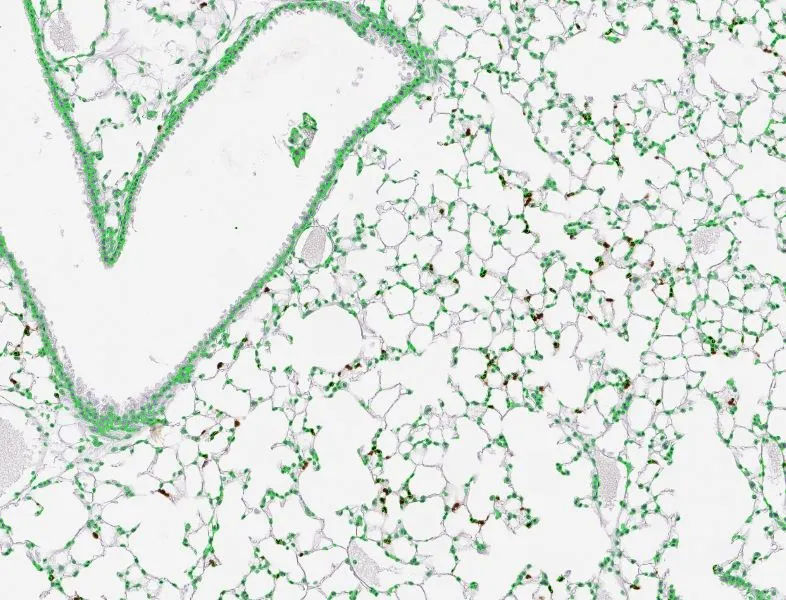

From Figure 7. USP2a contributes to tumor immunosuppression in immune-competent C57BL/6 mice and B7–H4 is involved in this process.Youwei Lu, Yu Sun, Jie Zhang, Miao Kong, Zhiming Zhao, Boshu Sun, Yuan Wang, Ying Jiang, Shaomu Chen, Chao Wang, Yin Tong, Liangzhu Wen, Moli Huang, Fengying Wu, Liang Zhang. The deubiquitinase USP2a promotes tumor immunosuppression by stabilizing immune checkpoint B7–H4 in lung adenocarcinoma harboring EGFR-activating mutants, Cancer Letters.

To further explore this, the team studied the role of USP2a on tumor growth in immunodeficient mice. These models confirmed that USP2a promotes tumor growth, regardless of B7-H4 expression in EGFR-MT lung cancer. By contrast, in immunocompetent mice, USP2a knockdown inhibited tumor growth, and B7-H4 overexpression resulted in tumor growth. Using multicolor immunofluorescence, they showed that knocking down USP2a increased the infiltration of effector T cells and decreased the infiltration of exhausted T cells. B7-H4 was able to reverse this effect, demonstrating that it can mediate the role of USP2a in the tumor microenvironment.6

In this study, the team employed TissueGnostics TissueFAXS cytometry to capture high-resolution tissue specimens coupled with TissueGnostics StrataQuest software to perform protein expression analysis. In particular, StrataQuest software enabled the spatial analysis of effector and exhausted T cells in relation to tumor cells.

Both tools are ideal to support spatial analysis in cancer research. TissueFAXS enables researchers to perform automated whole-slide multispectral imaging of up to 120 standard-size slides and up to 8 markers in one run. Meanwhile, StrataQuest can automatically detect and quantify cells and biomarkers in tissue sections of any origin, offering statistical analysis and integration with other bioinformatics tools within a user-friendly interface.